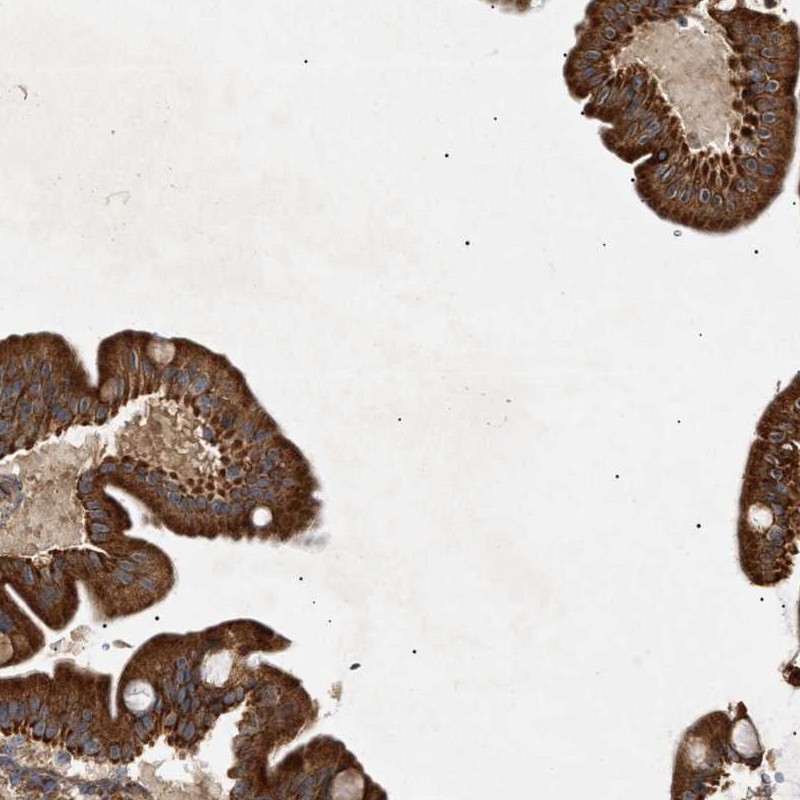

Immunohistochemical staining of human duodenum shows cytoplasmic positivity in glandular cells.